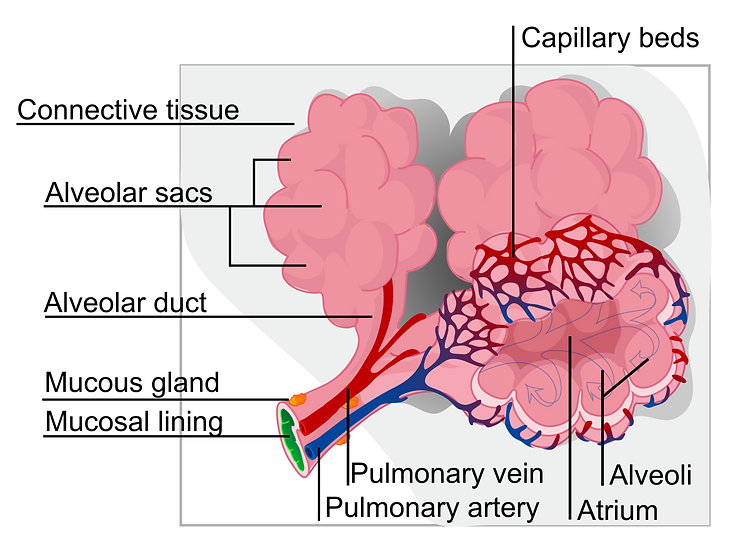

The alveolus of the lung (plural: alveoli, from Latin alveus, “little cavity”), is a tiny structure within the lungs measuring approximately 200 micrometers, or just a fraction of a centimeter. These tiny alveoli are bunched together in grape-like clusters to form alveolar sacs. On the surface of the alveoli are networks of tiny blood vessels called capillaries. It is through these tiny capillaries that airway oxygen from the air you inhale diffuses into the blood stream as a result of partial pressure. At the same time, carbon dioxide, the waste product of respiration, moves from the capillaries into the alveoli and out through the airways of the lungs where it is blown out with the next exhalation. [2]

One of the purposes of the red blood cells is to remove highly toxic and acidic cellular metabolic waste in the form of carbon dioxide and lactic acid and to pick up oxygen for delivery to cells for normal functioning. The process is called cellular respiration or oxygenation which takes place in the alveolar sacs of the lungs.

In order for the red blood cells to remove acidic metabolic waste and to pick up life giving oxygen they must pass through the pulmonary vein and then into the capillary pools. If the red blood cells are in pathological coagulation or aggregation there is no way to enter. Why? Because the entry into the capillary venules that branch off from the pulmonary vein measure 3 to 5 microns (1 micron is 1/25,000 of an inch – See Micrograph 1) and a single red blood cell measures 7 microns which makes it impossible for the red blood cell to enter the capillary venules if they are aggregated or coagulated into groups of red blood cells! [4]

When red blood cells group or clot together into a fibrin net, a clotting protein created when there is injury to the cell membrane and/or endothelial cells that protect the lining of blood vessels, (See Picture 2) the red blood cells cannot enter into the pulmonary vein and then into the capillary pools to release their acidic carbon dioxide waste and pick up oxygen in the alveolus of the lungs. (See Illustration 1)[5]

Pathological blood coagulation or disseminated intravascular blood coagulation (DIC) inside the pulmonary vein will prevent the free passage of red blood cells into the alveoli of the lungs via the pulmonary capillaries. {See Phase Contrast Micrograph 3 and 4) Erythrocytes or red blood cells must go into the pulmonary capillaries single file. If they cannot pass into the pulmonary capillaries of the lung to the alveoli this will cause oxygen deprivation that leads to red blood cell hypoxia (carbon dioxide poisoning) degeneration, genetic mutation, sepsis and sudden death.[6][7][8]